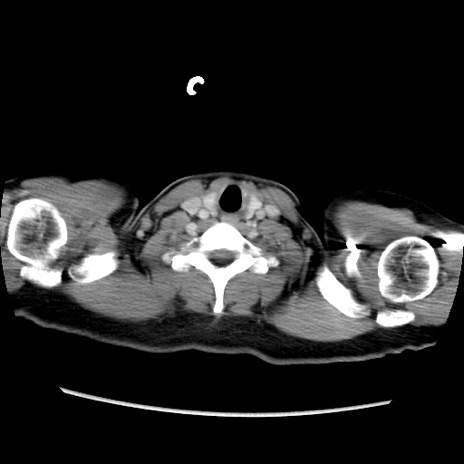

症例39(横断像)

【症例】40歳代女性

【主訴】上下腹部痛

【現病歴】2日目から下腹部痛あり。夜間は痛みで眠れなかった。昨日より上腹部痛と下痢が出現。臥位で痛みは軽快したため、休んでいた。本日になって臥位でも立位でも痛みが強くなってきたため救急要請。

【既往歴】子宮内膜症

【身体所見】部:平坦・軟、左上下腹部に圧痛あり、反跳痛あり。

【データ】WBC 21800、CRP 26.78